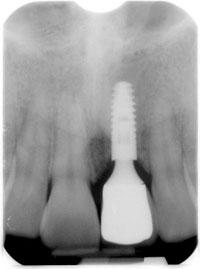

ภาพฟิล์ม X-Ray

วิวัฒนาการของรากฟันเทียมก้าวหน้าไปมาก จากเดิมเมื่อ 30 ปีที่แล้ว มาจนถึงทุกวันนี้ความก้าวหน้าทางทันตกรรมทำให้เราสามารถใช้รากฟันเทียมเล็กๆ 1 ราก ขนาดเส้นผ่าศูนย์กลาง 3.3 มิลลิเมตร และความยาว 11 มิลลิเมตร โดยทำให้มีพื้นที่ของผิวทั้งหมดเท่ากับรากฟันกรามธรรมชาติ 2 ราก รากฟันเทียมที่กล่าวถึงนี้มีประสิทธิภาพของการยึดเกาะระหว่างรากฟันเทียมกับกระดูกขากรรไกรมีความแข็งแรงมั่นคงดีขึ้นกว่ารูปแบบเดิมๆ ของรากฟันเทียมในสมัยก่อนมาก

ดังนั้น ถ้ากระดูกของผู้รับการรักษามีความแข็งแรงดี ทันตแพทย์สามารถใส่รากฟันเทียมและใส่ฟันในวันเดียวกันได้ และในกรณีปกติ ทันตแพทย์จะรอหลังจากฝังรากฟันเทียมไว้ประมาณ 6 – 8 อาทิตย์ แทนที่จะเป็น 4 – 6 เดือน เหมือนอดีตที่ผ่านมาใช้เวลาน้อยลง แต่ความงามเพิ่มขึ้น